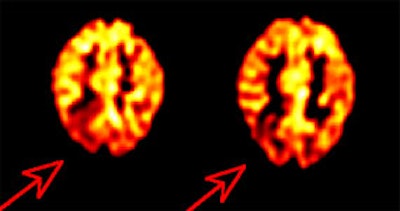

Alzheimer's disease on FDG PET: The case below is from an 86 year old male being imaged to exclude Alzheimer's disease. The FDG PET exam demonstrated bilateral temporoparietal hypometabolism. This finding is very sensitive for the diagnosis of Alheimer's disease. The exam was performed on an ECAT EXACT HR+ PET scanner (manufactured by CTI) after administration of 108 MBq FDG. The exam was acquired using a 3D dynamic emission and 15 minute transmission protocol. Case courtesy of Institut fur Medizin Forschungszentrum Julich, Germany and CTI PET Systems, Inc. |